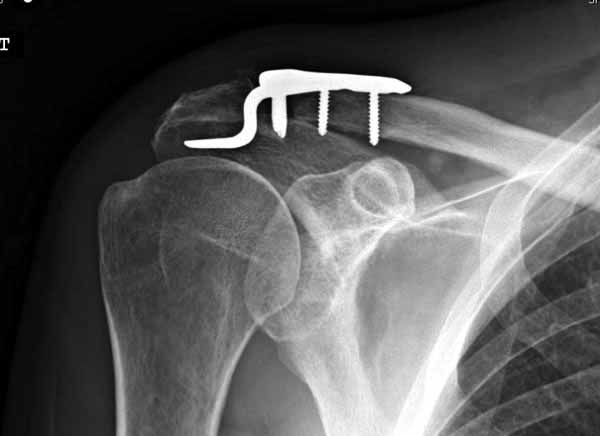

Из заданного вопроса в этом посте я понял, что разговор идет по поводу “методики применения ключичной пластины с крючком при акромиальных переломах”, т.е не ведется разговор “по поводу лечения косых переломов ключицы”.

Если так, тогда Юрий прав, методов лечения акромиона пластинами нельзя было найти. Обычно изобретали из реконструкционных пластин 2.7 или 2.4 мм толщиной. Такая фиксация адекватно удерживает перелом акромиона. Только недавно компания Acumed создала пластину для переломов акромиона, здесь линк: http://www.acumed.net/sites/default/files/literature/brochure-surgical-technique/CPS00-11-A.pdf.

По поводу пластины с крючком, Ваше заключение "не вижу препятствий для фиксации акромиального косого перелома ключицы для МОС использовать пластинку с крючком" вызывает сомнение.

Предназначенную для лечения повреждений связочного аппарата акромиально-ключичного сочленения пластину можно применить не при всех переломах акромиального конца ключицы. Потому что имплант рассчитан на интактную ключицу и не для переломов ключицы. Пластина короткая, не покрывает медиальный диафизарный фрагмент ключицы и за счет тракции стерноклеидомастоидеус такая фиксация прорвется через несколько дней.